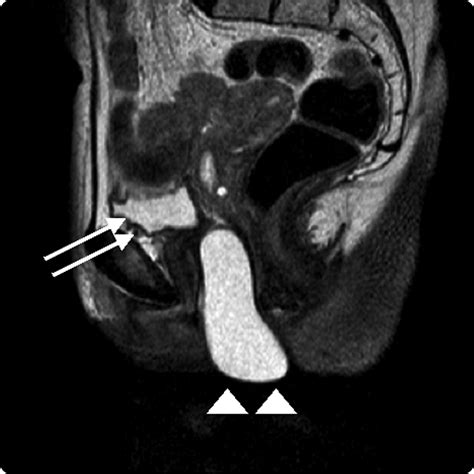

Diagnosing a Gartner’s duct cyst typically begins with a physical pelvic examination. A clinician will visually inspect and palpate the vaginal wall to assess the location, size, and consistency of the mass. Because these cysts are typically located along the anterolateral wall of the vagina, their position is a key diagnostic indicator.

To confirm the diagnosis and rule out other conditions—such as a Bartholin's gland cyst, a urethral diverticulum, or a vaginal wall malignancy—imaging studies are often utilized:

Imaging Method Purpose in Diagnosis

Transvaginal Ultrasound First-line imaging to visualize the cyst's fluid content and exact location.

Pelvic MRI Provides superior soft-tissue detail, helping to determine the origin and relation to nearby structures.

CT Scan Useful for larger cysts to assess for potential compression of adjacent pelvic organs.

⚠️ Note: Imaging is essential to accurately distinguish between a benign Gartner's duct cyst and more complex pelvic masses that may require more intensive surgical intervention.